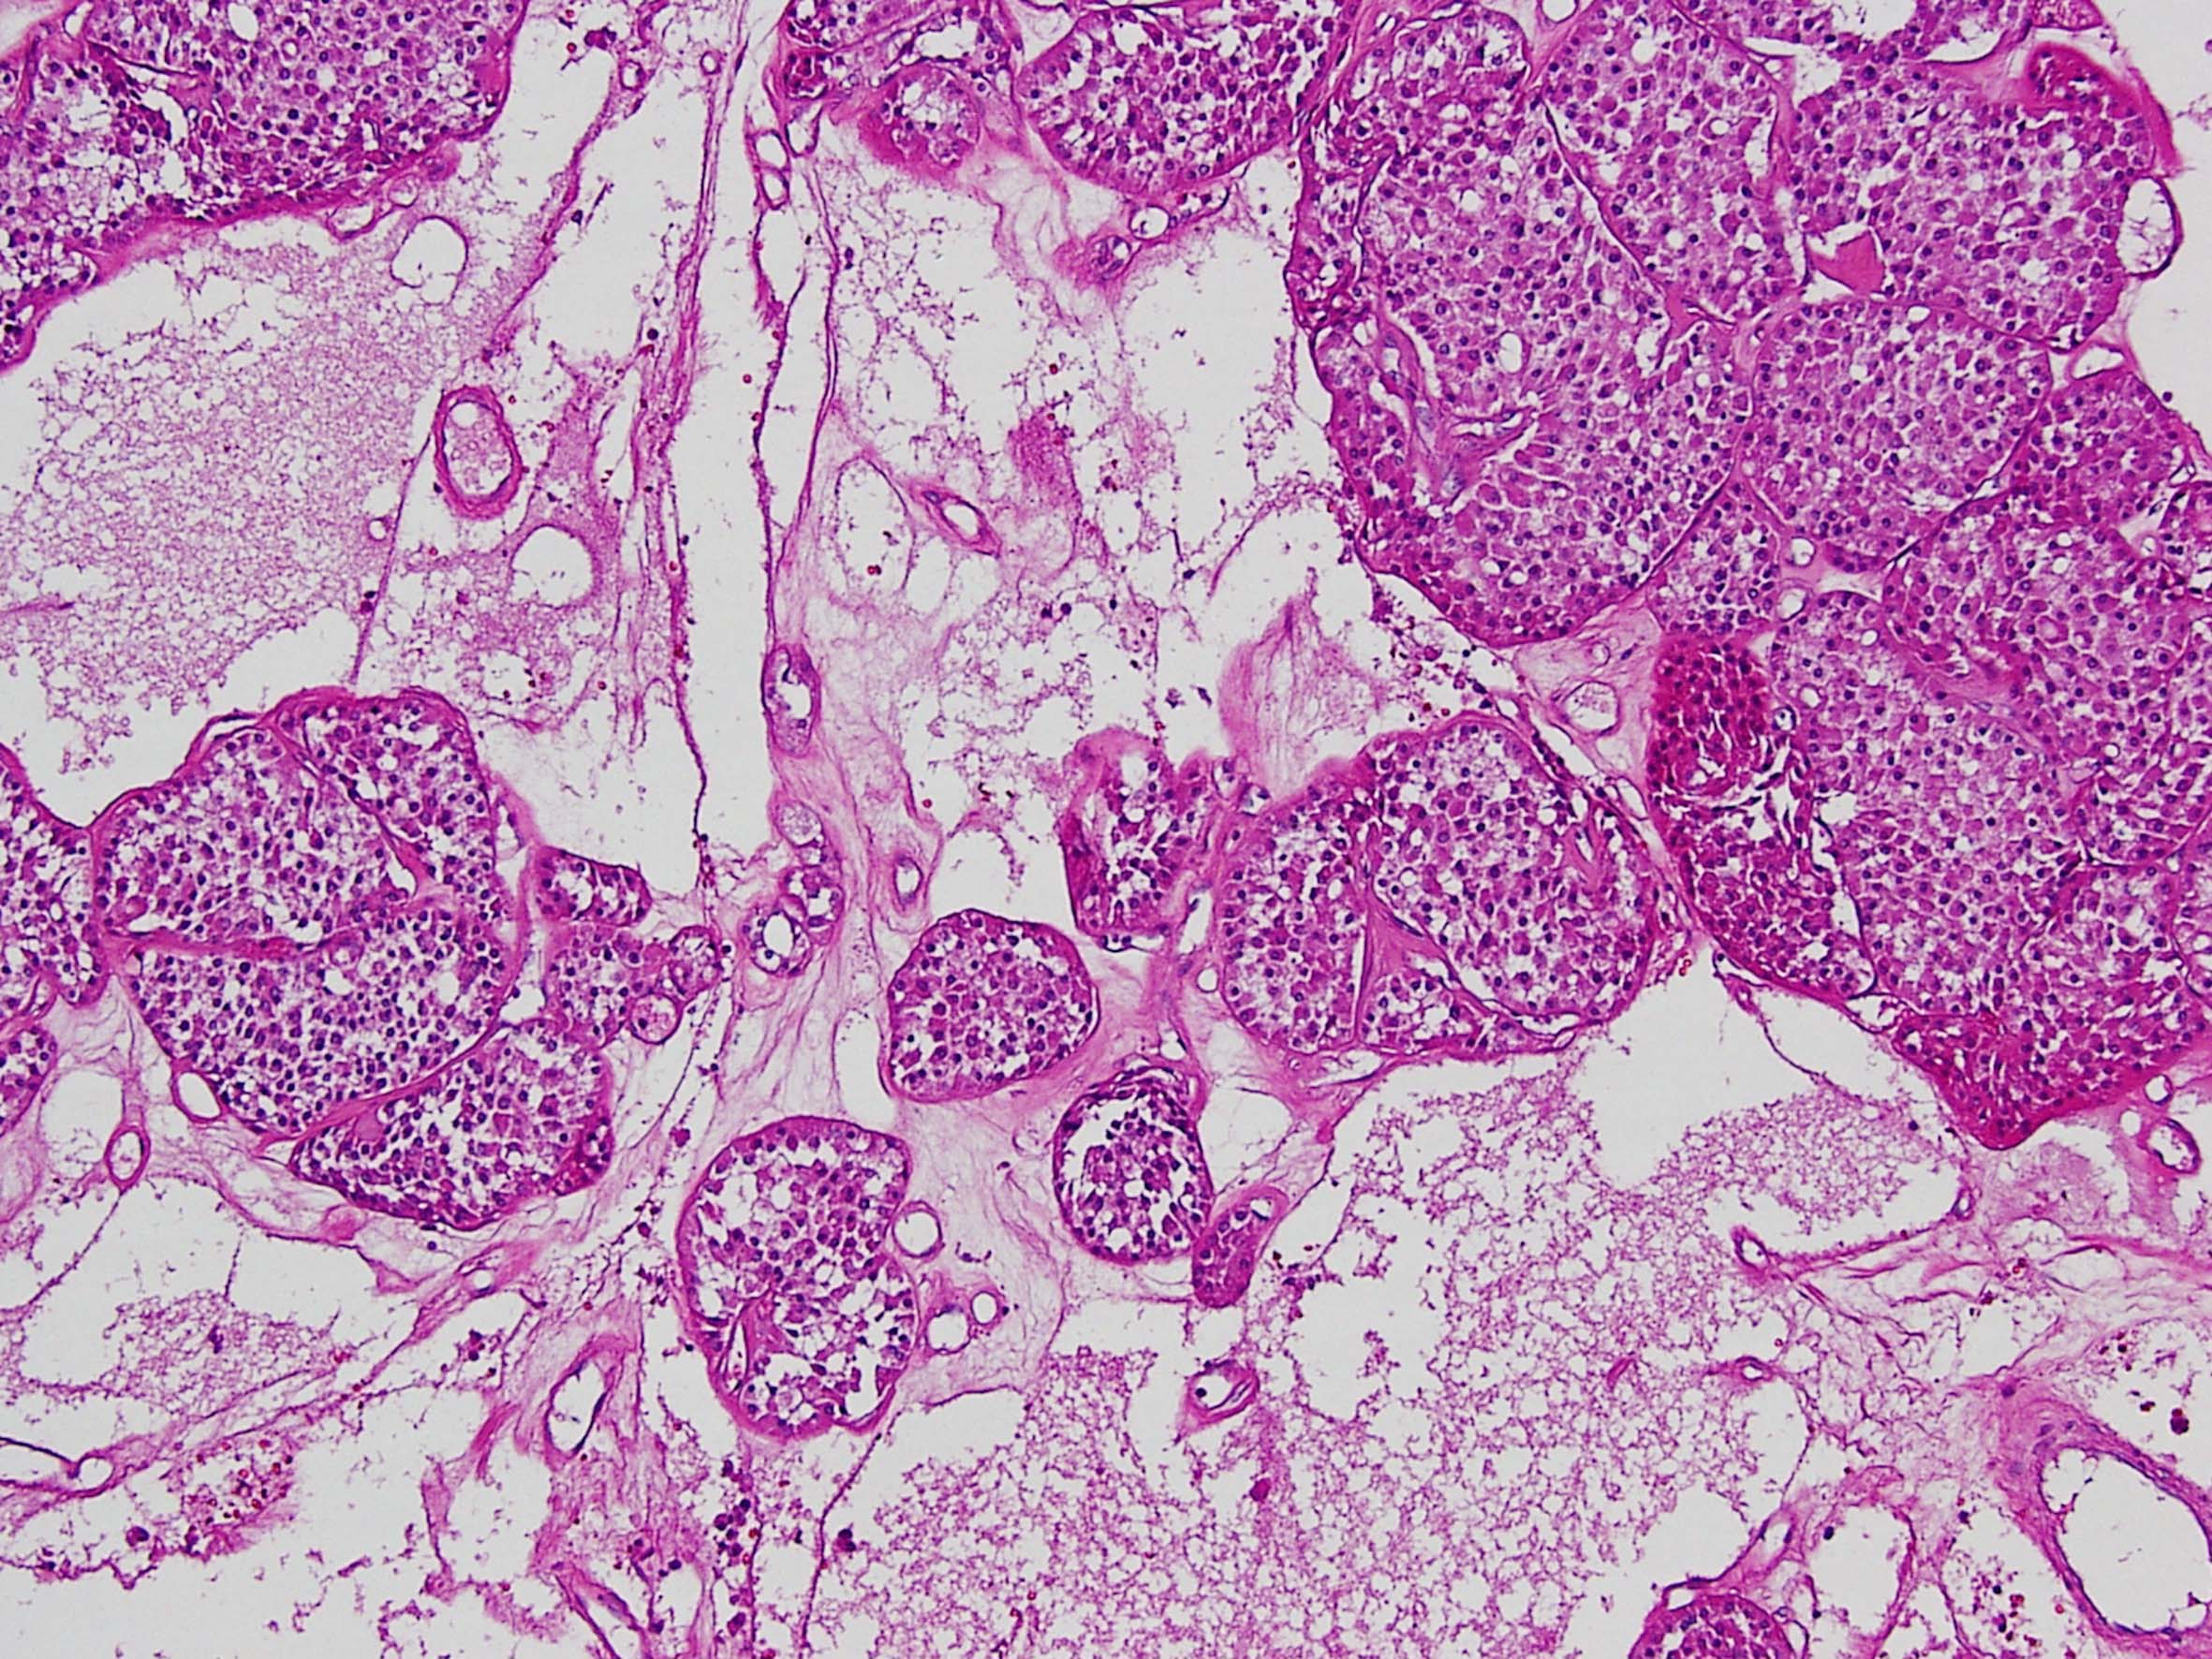

Renal tumor grading

Case ID: 290